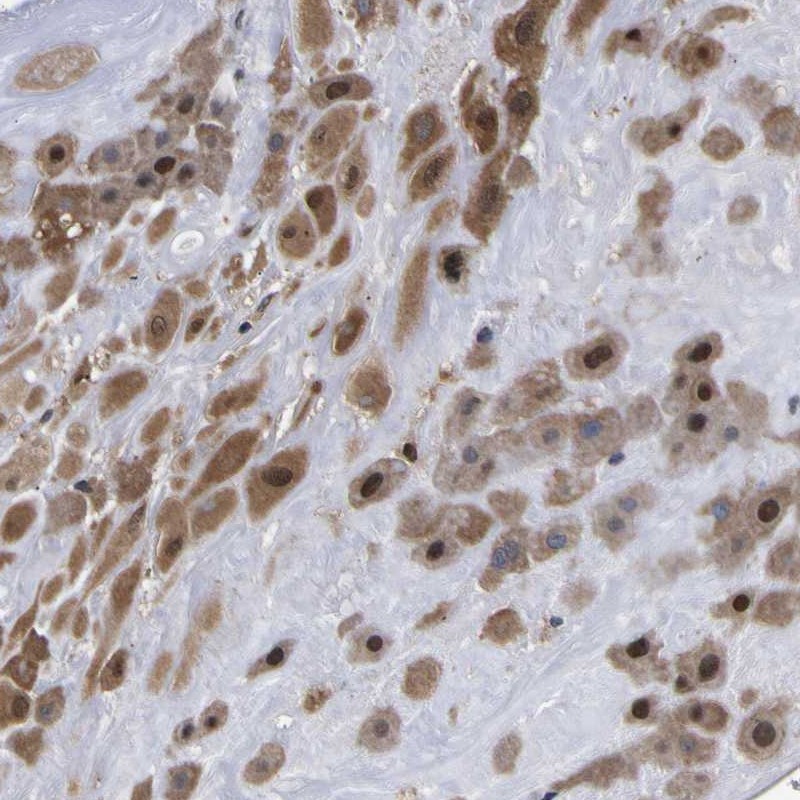

Immunohistochemical staining of human placenta shows cytoplasmic and nuclear positivity in decidual cells.